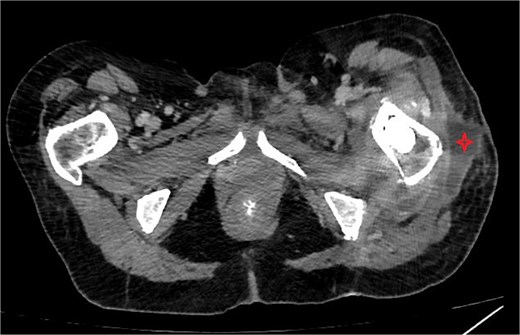

One week after the second stage DAIR, lab tests showed WBC 7500 (63% neutrophils), ESR 102, and CRP 48. CT abdomen and pelvis with IV contrast at 2 weeks did not show any intraabdominal collection or fistula suspicious of primary source of seeding, however it showed fluid collection in the left psoas muscle extending to the iliacus (8.7 × 2 × 1.5 cm), suggestive of deep abscess formation (Fig. 5) with superficial collection in vicinity of left proximal femur (Fig. 6). The latter collection was superficial and was drained at the bedside, releasing non-purulent fluid. The deep abscesses were drained by interventional radiology and a pigtail catheter was inserted for 1 week. Cultures from the deep collection grew K. pneumoniae susceptible to meropenem, which was used to replace ceftriaxone.

CT abdomen/pelvis showing rim enhancing fluid collection (marked with circle) in the left psoas muscle (left image) with extension to the left iliacus (right image) measuring 8.7 × 2 × 1.5 cm, suggestive of abscess formation.

CT abdomen/pelvis showing subcutaneous collection at the upper lateral aspect of the thigh in the vicinity of the left proximal femur.